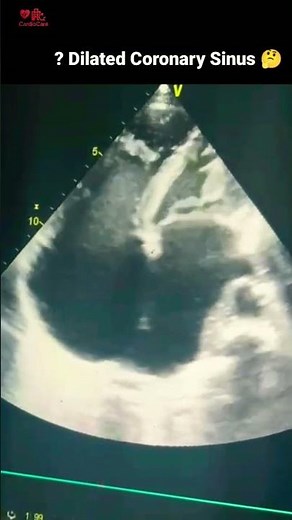

Function - How to Assess Coronary Sinus by

Echo